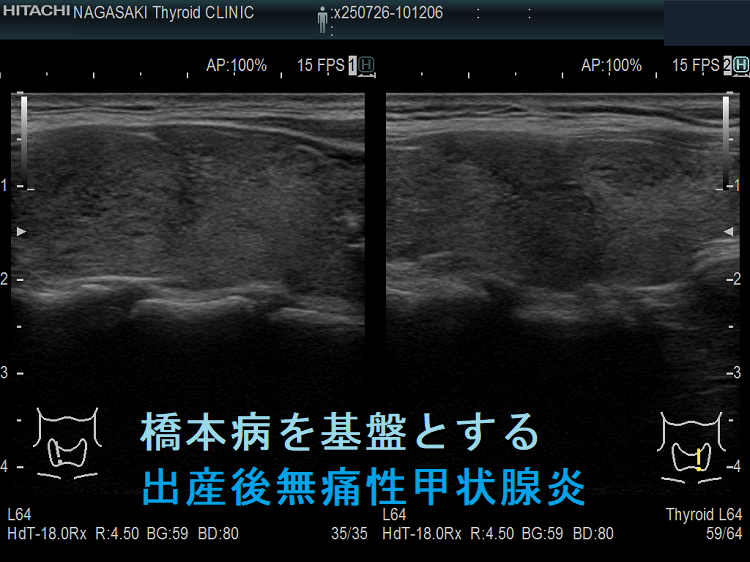

橋本病を基盤とする出産後無痛性甲状腺炎(水平断) ドプラーモード;無痛性甲状腺炎であるため、内部血流は少ない。

橋本病を基盤とする出産後無痛性甲状腺炎下甲状腺動脈の収縮期最大血流速度(ITA-PSV);無痛性甲状腺炎であるため、下甲状腺動脈の収縮期最大血流速度(ITA-PSV)は低値